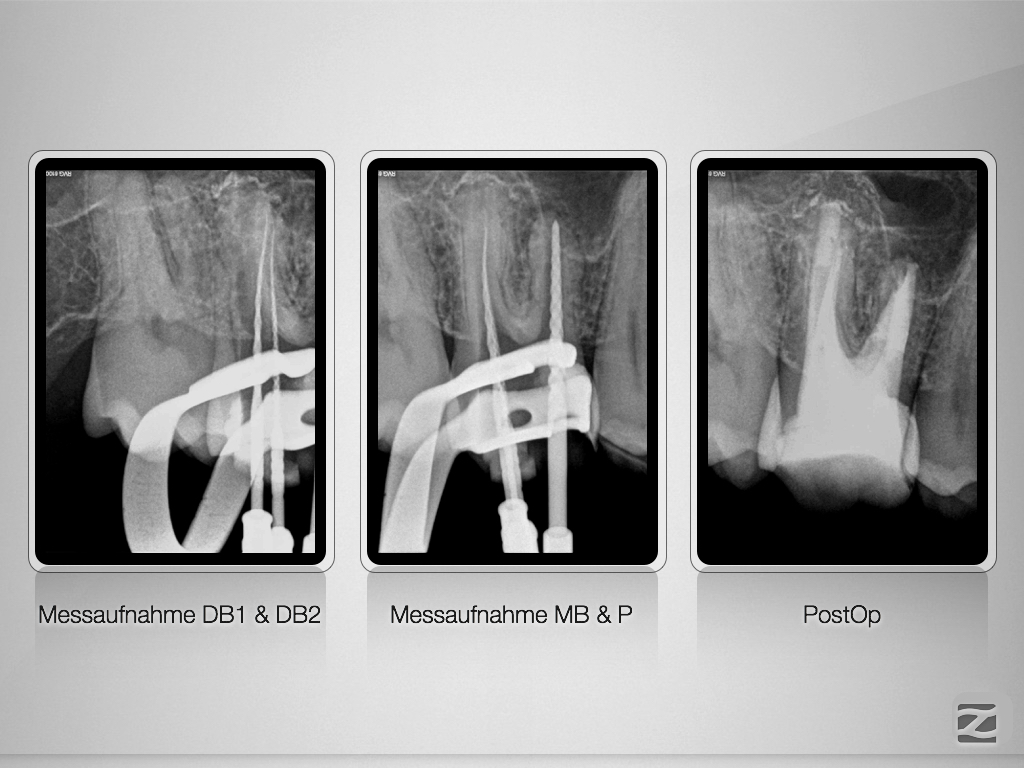

16D.011

Multiple Fragmente